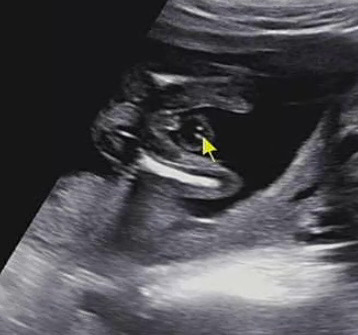

다리사이를 잘보여준 아가!

🌶️존재감 뿜뿜이예요🙈 귀엽죠!? 16주인데 반전없겠죠? 남편이 너무 좋아해요ㅋㅋㅋㅋ

쩍벌 아들입니다ㅋㅋㅋ고맙습니당😝